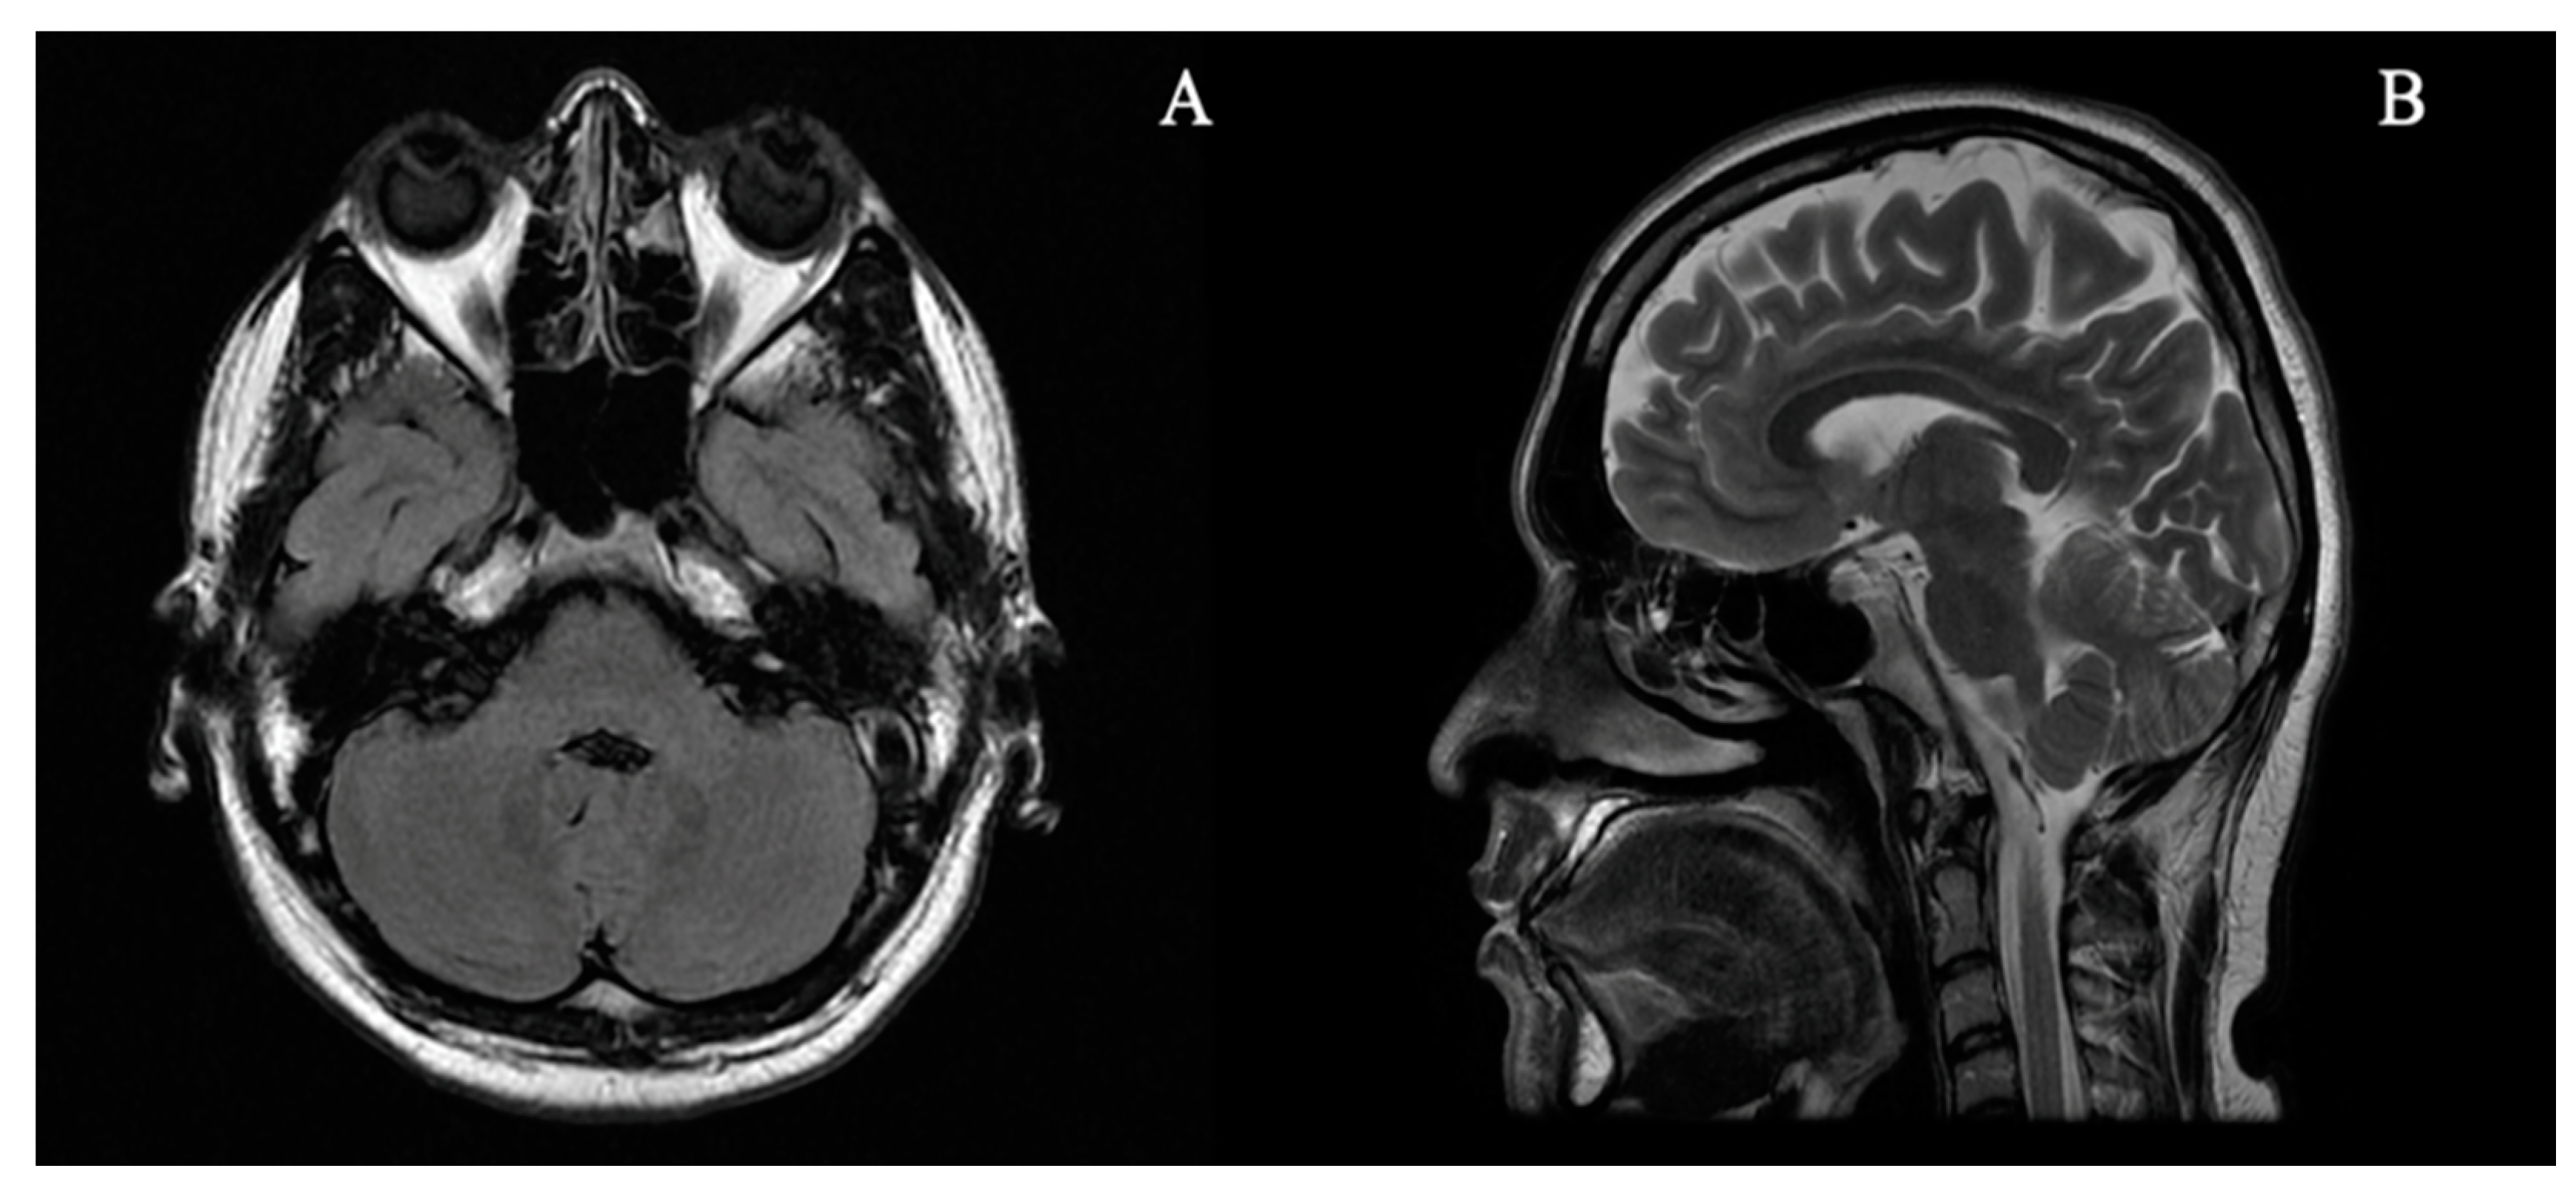

2. Case Report